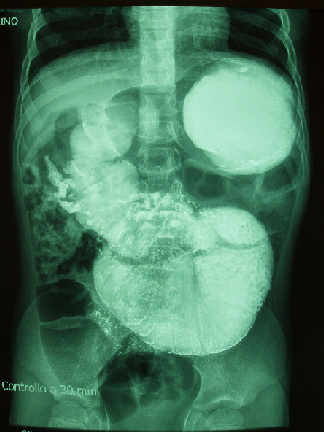

Per riacutizzazione degli episodi di vomito il paziente � stato nuovamente condotto al Pronto soccorso, dove sono stati eseguiti esami ematici che sono risultati sempre nella norma. L�obiettivit� clinica risultava assimilabile a quella precedentemente riscontrata, con marcata distensione addominale e rilievo di anse palpabili. Il radiogramma diretto dell�addome eseguita in regime di ricovero ha mostrato dilatazione dello stomaco e di alcune anse intestinali, presenza di livelli idroaerei e di residui fecali, prevalentemente a livello colico. All�Ecografia dell�addome si evidenziavano anse intestinali distese da contenuto ipoecogeno e gastrectasia con stomaco ripieno di ingesti, senza evidenza di falde fluide. Dati questi reperti, � stata effettuato uno studio radiologico dell�intestino tenue con mezzo di contrasto che ha mostrato disposizione trasversale dello stomaco, regolare disposizione del duodeno, che si presentava tuttavia notevolmente e persistentemente dilatato, Treitz collocato a sinistra dei corpi vertebrali ma pi� in basso rispetto al bulbo duodenale, anse del tenue prossimale persistentemente dilatate e disposte centralmente. Le anse del restante tenue prossimale presentavano invece calibro regolare, ma risultavano disposte a destra, dunque in sede insolita (Figura 1). Quanto evidenziato poneva sospetto per anomalia di rotazione intestinale atipica. L�RX clisma opaco ha messo in evidenza colon di dimensioni e posizione regolari. E� stata decisa l�esecuzione di intervento chirurgico. Al tavolo operatorio � stato confermato il sospetto di malrotazione intestinale. Sono state infatti reperite numerose briglie di Ladd, considerevole brevit� della radice del mesentere e collocazione di duodeno e anse del tenue prossimale (compreso il passaggio duodeno-digiunale) nei quadranti di destra dell�addome. La non concordanza dei reperti intraoperatori con le immagini dell�esame radiologico � verosimilmente dovuta alla dislocazione a sinistra del passaggio duodeno-digiunale durante l�indagine diagnostica, secondaria all�estrema dilatazione delle anse, allo sfiancamento di parete delle stesse e alla necessit� di utilizzare considerevoli quantit� di mezzo di contrasto.Il paziente � stato quindi sottoposto a intervento di derotazione intestinale laparotomica. Date le dimensioni del duodeno si � proceduto a rimodellamento del megaduodeno tramite tapering antimesenterico. E� stata effettuata inoltre la riparazione dell�ernia ombelicale, attraverso l�accesso laparotomico.

Figura 1. Immagine di studio radiologico del tratto digerente con pasto baritato in cui � possibile apprezzare la notevole distensione del duodeno e delle anse prossimali dell�intestino tenue. L�angolo duodeno-digiunale di Treitz (freccia) � collocato a sinistra dei corpi vertebrali ma pi� in basso rispetto al bulbo duodenale.